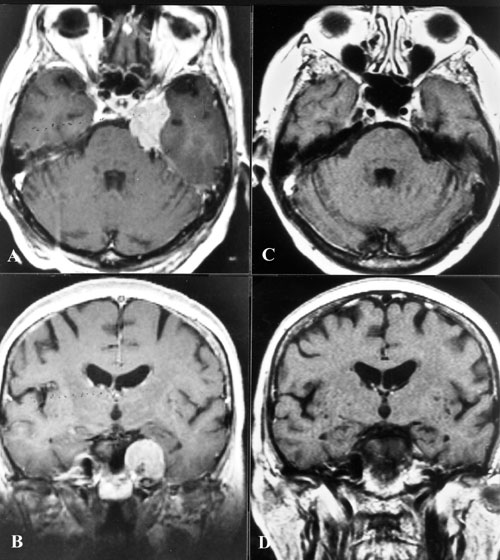

• 脑膜瘤的典型CT表现是什么?脑膜瘤MRI表现有哪些?

脑膜瘤的典型CT表现是什么?脑膜瘤MRI表现有哪些?

2021-08-04 10:48:50

脑膜瘤生长缓慢,常压迫周围组织引起相应的神经症状和体征,造成不同的障碍与肿瘤部位有关。脑膜瘤的典型CT表现是什么?脑膜瘤MRI表现有哪些?...